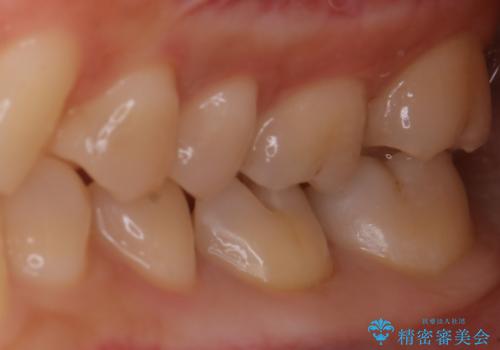

適合のよいセラミックで自分の歯となじむ自然な仕上がりに

- 大きく口を開けると目立つ銀歯のやり替えをご希望された患者様です。適合のよいセラミックインレーで補綴することで、将来的な虫歯発生のリスクを最小限に抑え、機能面でも安心して使っていただけるようにしました

適合不良の補綴物は二次的な虫歯発生のリスクが高まります。

自費診療で用いられる材料は保険適応の材料に比べて、より精密で適合の良い被せ物作ることができるため、長期的な虫歯のリスクを大幅に減らすことが可能です。